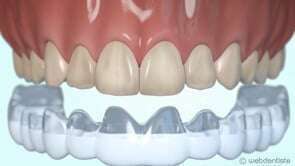

Pour certains patients, et plus particulièrement pour le patient adulte, le souci d’esthétique pendant le traitement est un élément majeur à prendre en compte. Cette orthodontie peut s'effectuer de trois manières.